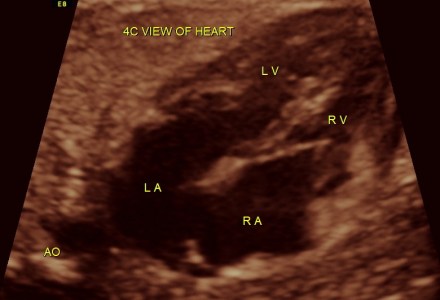

Can Ostium Secundum Atrial Septal Defect diagnosed antenatally ?